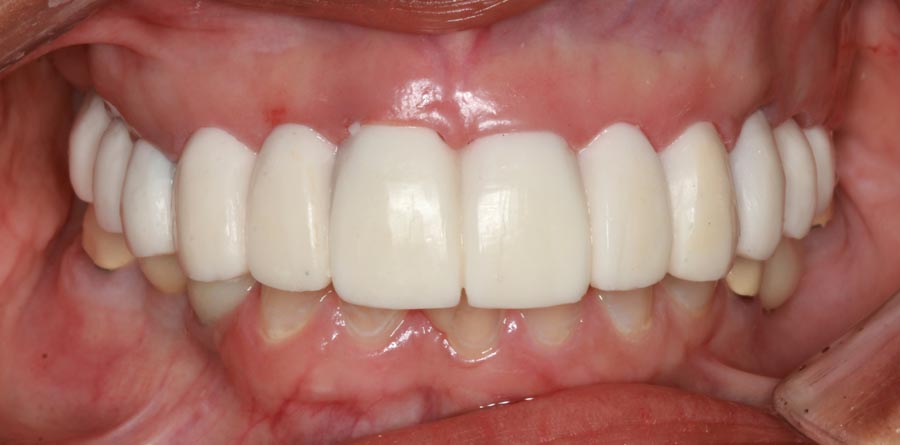

Smile GalleryImplant RestorationsFull Mouth Implant Restoration Full arch zirconia implant bridge (full smile) 1 of 37 Pre-op full smile Pre-op lips retracted Pre-op panoramic x-ray Extraction of strategic teeth Placement of implants Extraction of some remaining teeth after verification of adequate implant stability Occlusal view Post-op panoramic x-ray Immediately fabricated provisional restoration (tissue side view) Immediately fabricated provisional restoration (occlusal side view) Immediate provisional delivered on day of surgery Immediate provisional 2 weeks later Scalloped tissue developed from the provisional at 2 weeks Jig used for making a master impression Provisional in place (full smile) Provisional in place (lips retracted) Provisional in place (right side) Provisional in place (left side) Wax try-in (full smile) Wax try-in (right side full smile) Wax try-in (left side full smile) Wax try-in (full face, lips together) Wax try-in (full smile) Wax try-in (right side) Wax try-in (left side) Wax try-in (lips retracted) Full arch zirconia implant bridge on master cast (frontal view) Full arch zirconia implant bridge on master cast (occlusal view) Implant positions and soft tissue representation on master cast (occlusal view) Soft tissue representation on master cast (frontal view) Full arch zirconia implant bridge (tissue side view) Soft tissues on day of delivery (occlusal view) Soft tissues on day of delivery (frontal view) Full arch zirconia implant bridge delivered (lips retracted) Full arch zirconia implant bridge (lips retracted, close up) Post treatment panoramic x-ray Full arch zirconia implant bridge (full smile)